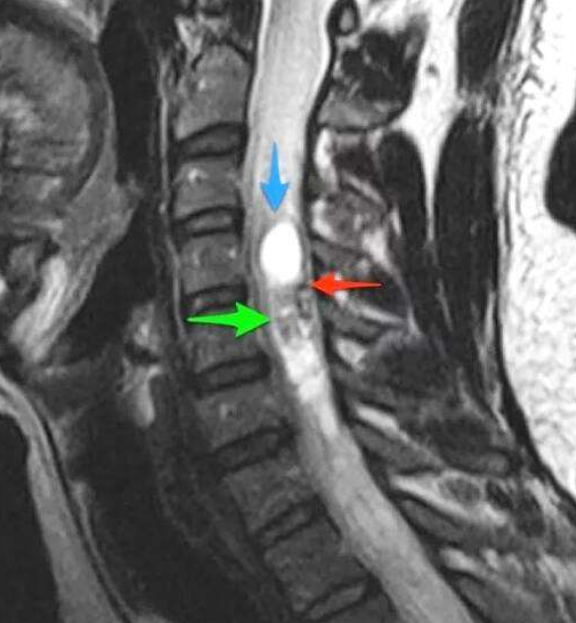

脊髓肿瘤影像学图

髓内-髓外-肿瘤位于脊髓的薄层(硬脑膜)内,但在实际的脊髓外。在这个地方发生的频率是40%。较常见的这些类型的肿瘤发生在脊髓的蛛网膜(脑膜瘤)、从脊髓延伸出的神经根(神经鞘瘤和神经纤维瘤)或脊髓基底(终丝室管膜瘤)。虽然脑膜瘤通常是良性的,但它们很难切除并可能复发。神经根肿瘤通常也是良性的,尽管神经纤维瘤随着时间的推移可能变成恶性的。脊髓末端的室管膜瘤可能很大,该区域细致的神经结构的微妙特性可能使切除变得困难。

髓内-这些肿瘤生长在脊髓内。它们通常来源于神经胶质细胞或室管膜细胞(一种神经胶质细胞),这些细胞遍布于脊髓的间质。在这个地方发生的频率大约是5%。星形细胞瘤和室管膜瘤是较常见的两种类型。星形细胞瘤多见于胸段,其次为颈段。室管膜瘤较常见于丝(脊髓底部),其次是颈段。它们通常是良性的(与颅内相比),但是很难切除。

硬膜外-肿瘤位于硬脑膜外,硬脑膜是围绕脊髓的一层薄薄的覆盖物。该地区与上述地区的发生率约为55%。这些病变通常是由于转移性癌症或较少见的神经鞘瘤来自覆盖神经根的细胞。有时,硬膜外肿瘤通过椎间孔,部分位于椎管内,部分位于椎管外。